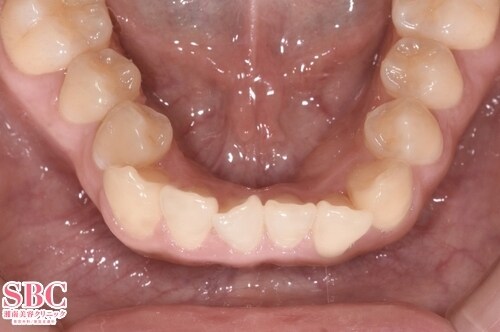

No.309340【美容歯科】の症例写真

施術前

施術後10ヶ月後